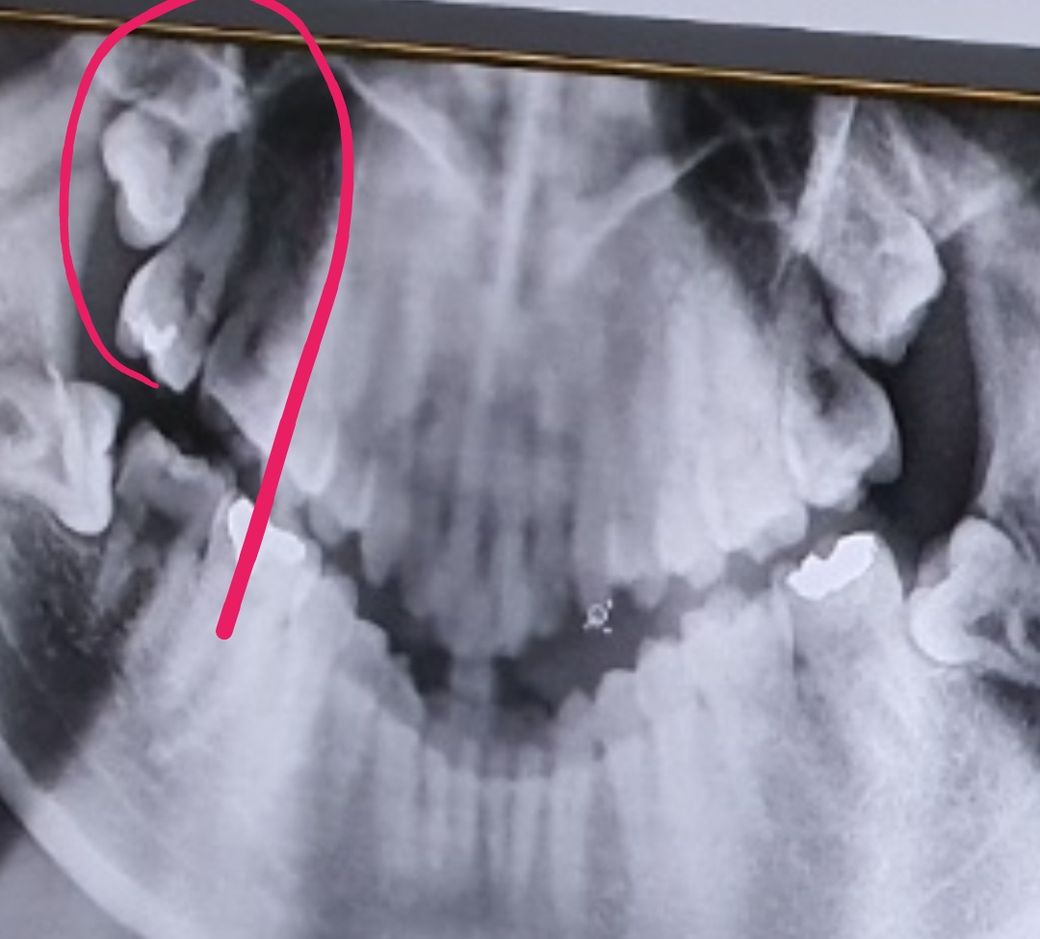

4년전 찍은 엑스레이이인데요 저기 윗쪽 이빨이 조금씩 자라나고 있는데 이 경우 옆 치아 안건드리면 발치 안해도 되지않나요? 궁금합니다. ㅠ

• 1번 째 사진

4년전에 찍은 사진만보면 특별한 이유가 없다면 발치를 하실필요는 없을것같습니다. 현재상태는 어떤지 모르지만 지금도 저상태라면 발치를 안하셔도 될것같습니다.

현재 위와 아래 사랑니 모두 방향이 틀어져서 나오고 있어 앞의 어금에 영향을 미칠수 있기에 가능한 빠른시일내에 모두 발치를 하는 것을 권합니다.

아래와 달리 위 치아는 특별히 막혀있지 않기 때문에 맹출력이 있는한 완전히 내려올 가능성도 있어보입니다

그때가서 관리가 어렵다면 발치해주면 됩니다